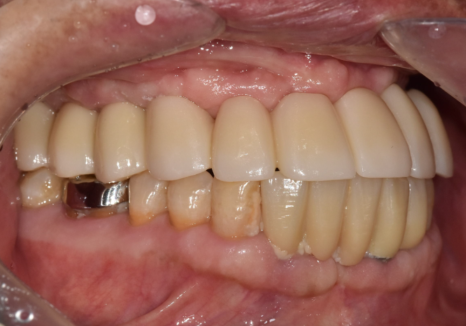

임플란트 6개를 연결하는 보철은

0.1mm만 틀어져도 문제가 생기는데,

디지털 데이터는

이런 오차를 최소화하기 때문에

보철의 완성도가 높다는게 최장점입니다.

그래서 이 환자분의 경우,

적절한 기준점에 맞게

임시 치아를 충분히 써보시게 했습니다.

임시치아를 써보시며

불편한 부분은 없었는지 확인하고,

안모 변화를 확인한 뒤에야

최종 보철을 완성했습니다.